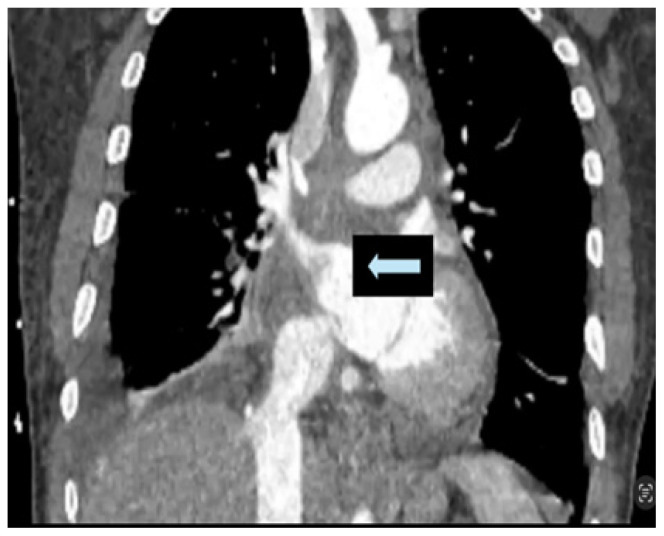

Metastatic Cardiac Angiosarcoma Presenting as Superior Vena Cava Syndrome and Cardiac Tamponade.